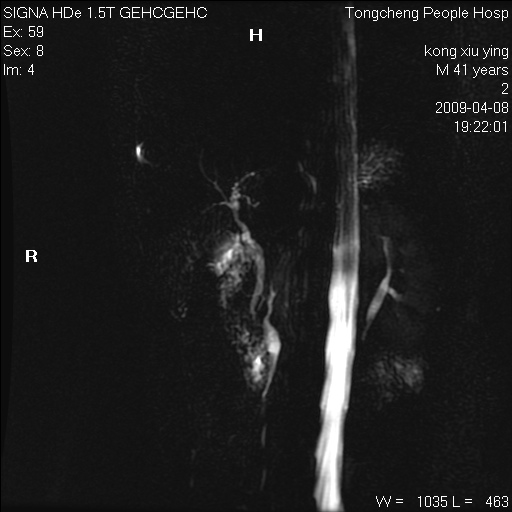

标题: CL1008:【经典】胆囊石榴籽样结石。

女,41岁。健康体检——彩超提示:胆囊显示不清。平素健康,无不适感。

腹部mr扫描及mrcp,图像如下: